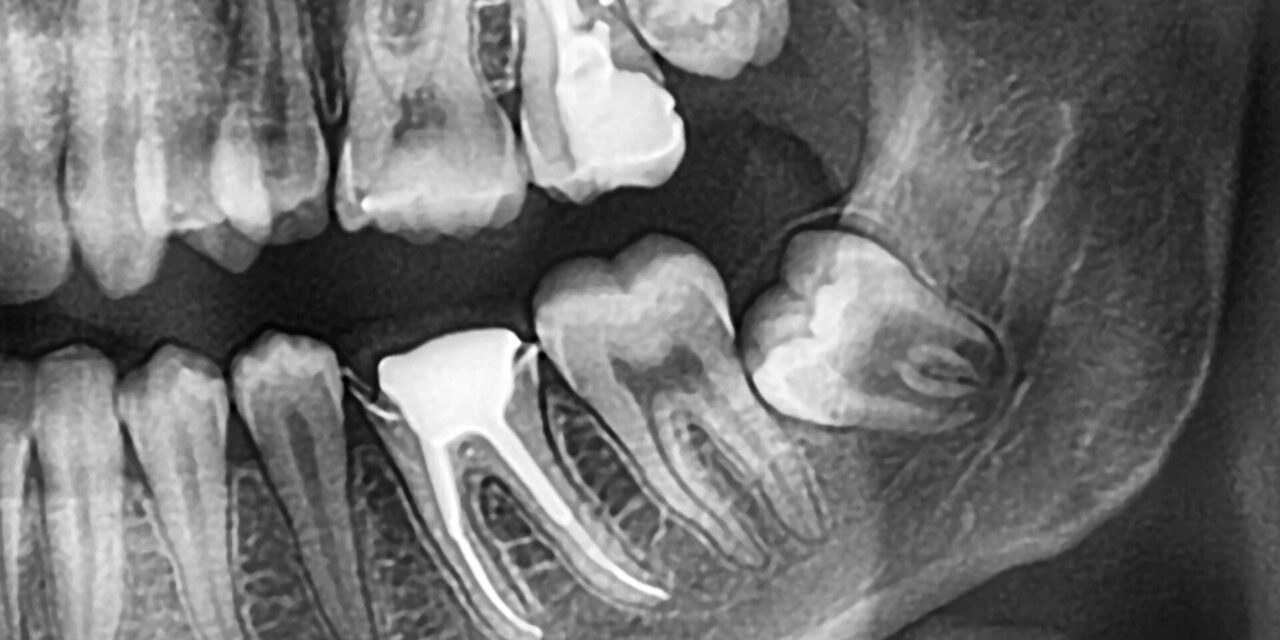

Distinguir el origen del dolor dental es fundamental para un tratamiento correcto. Si sientes una presión que empuja tus otros dientes, es una señal clara. En nuestra clínica, utilizamos escáneres intraorales 3D para visualizar la posición exacta del molar.

La tecnología diagnóstica avanzada nos permite ver si la muela está impactada. Esto ocurre cuando el diente no tiene espacio para salir y choca contra el segundo molar. Un diagnóstico preciso mediante tomografía CBCT evita confusiones con otras patologías.